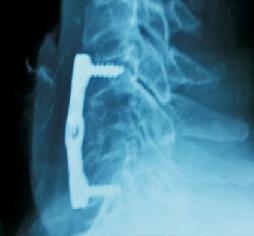

Odantoid Fracture

Facet Dislocation

Cervical Vertebral Fracture

Vertebral Injury